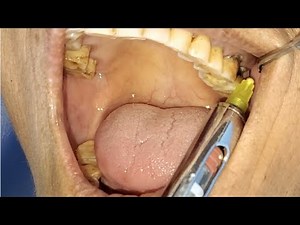

Top suggestions for Upper Molar Tooth Extraction |

Tooth Extraction - Upper Molar